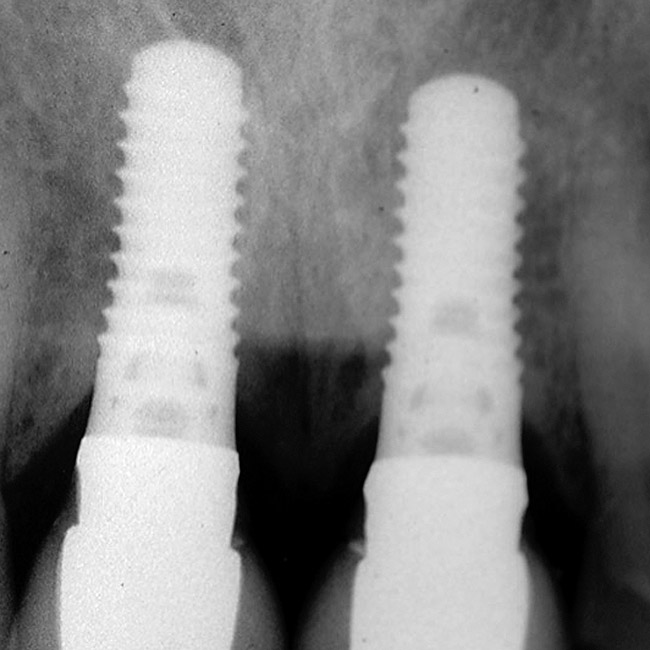

Figure 6  Excellent interproximal crestal bone level between the centrals before extraction.

Figure 6

Figure 8  Maintenance of interproximal crestal bone following final restoration placement.

Figure 8